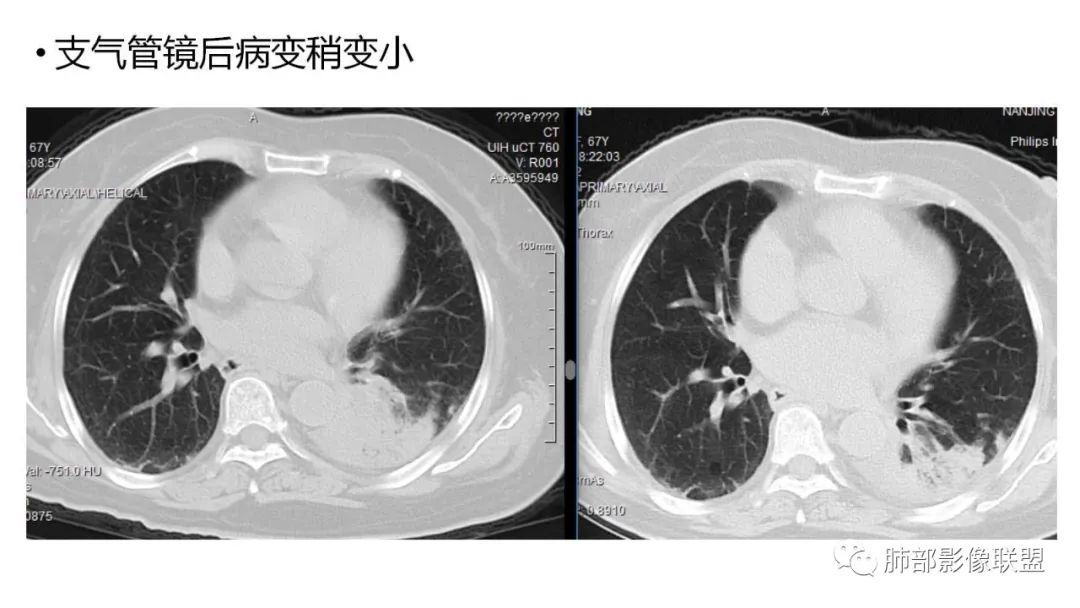

2、病灶常有一个主病灶,常位于下肺。后沿气道播散为多发病灶。

9.粘液腺癌的变化规律:结节缓慢发展而来,向周围播散形成斑片后可快速进展,有时支气管镜后或粘液排出后局部可形成好转的假象。病灶可沿肺泡和支气管播散。

4.回到本例,左下肺病变两次好转,均未经过肿瘤治疗,第一次是支气管镜后,第二次是当其他病变都在进展的情况下,左下肺病变范围反而缩小趋于浅淡。